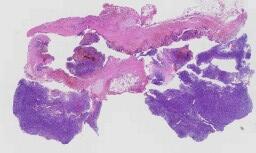

临床资料: 女,83岁,入院前1+年,因中上腹隐痛于外院胃镜检查提示:胃肿瘤,治疗好转后出院。10+天前患者因贫血于外院行胃镜提示:胃GIST,性质?经输血治疗后好转出院。现为手术治疗,以“胃间质瘤”收治入院。CT平扫+增强:胃幽门部胃壁不均质性并见团块状软组织密度影,较大横截面积约5.8cm×4.5cm,边界不清,其内见条状钙化灶,增强扫描后病灶明显不均匀强化,其内可见无强化坏死区。考虑肿瘤性病变。

大体所见: 带部分大网膜切除部分胃一个,紧邻幽门管浆膜下可见一灰白肿物,小大5.5cm×4.5cm×4cm,表面被膜光滑完整,切面灰红灰白,实性,质中,侵及黏膜下层。